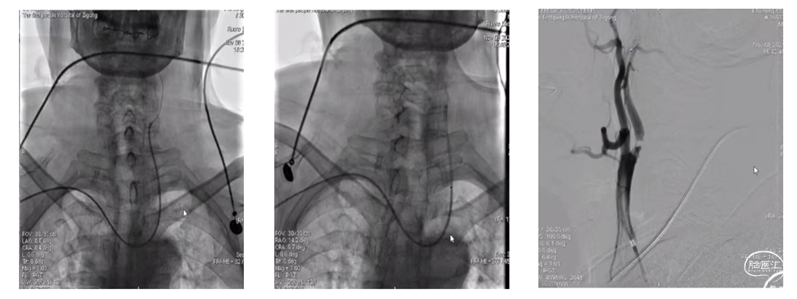

左侧颈动脉重度狭窄经桡动脉介入治疗

----北京市大兴区人民医院杨海华 陈娜 隋晓杰

Ⅲ型弓,经股动脉难以到位。

穿刺右侧桡动脉,置入6F桡动脉鞘,上5F猪尾造影导管,但很不巧,碰上了桡动脉环,但环不大,将导丝送到动脉环,跟进导管,再将导丝走远,动脉环就变直了,继续跟进导管。

1、通路建立

将猪尾造影导管送入主动脉弓,将260cm泥鳅导丝送入到降主动脉,撤出造影导管,沿导丝送入西蒙导管+6F导引导管组合,尝试将西蒙导管送入到降主动脉成绊未能成功,遂将头端较软的导引导管先送入到降主动脉,再送入西蒙导管,后撤导引导管,西蒙导管成绊,再选入左侧颈动脉,跟进导引导管,回撤西蒙导管,这时导引导管不稳,有下滑的趋势,遂先继续送入导引导管,再回撤西蒙导管,通路建立成功。

2、沿导引导管送入保护装置,释放后,尚导丝送入4-30mm球囊,予以6atm压力扩张,撤出球囊,造影示狭窄。

3、最关键的时刻来了,撤出球囊,沿导引导管送入8-40支架,在支架要过主动脉弓时,导管不稳,有下滑的感觉,远端的保护装置也往下移位,需要进行调整,将保护装置再往上送,缓慢的跟进导管到狭窄处,这样导管的支撑力就够了,再缓慢的送入支架,终于支架安全到位。

支架准确定位后,缓慢的后退导引导管,再缓慢的释放支架,在释放的时候还是有一点张力,释放较困难,需要给点力,支架释放完后,再沿支架输送器往上送导管,造影示有残余狭窄,予以PTA 5-30球囊扩张。

4、球囊扩张后,尚球囊送入导引导管通过支架至C1段远端,将保护装置回收。

本例患者为Ⅲ型主动脉弓,无名动脉与左侧颈总动脉几乎平行、左侧颈总动脉与主动脉弓也是很小的锐角,无论是从上肢入路还是下肢入路都很难建立通路;

本例患者存在经桡动脉入路的诸多障碍,但因患者的强烈需求,最终还是尝试经右侧桡动脉入路进行手术,最终顺利完成,道虽迁,行则将至,面对困难,需要面对,勇于尝试,才能不断进步,但术前也需要做好各种紧急预案,术中小心操作,将风险控制在最小程度。